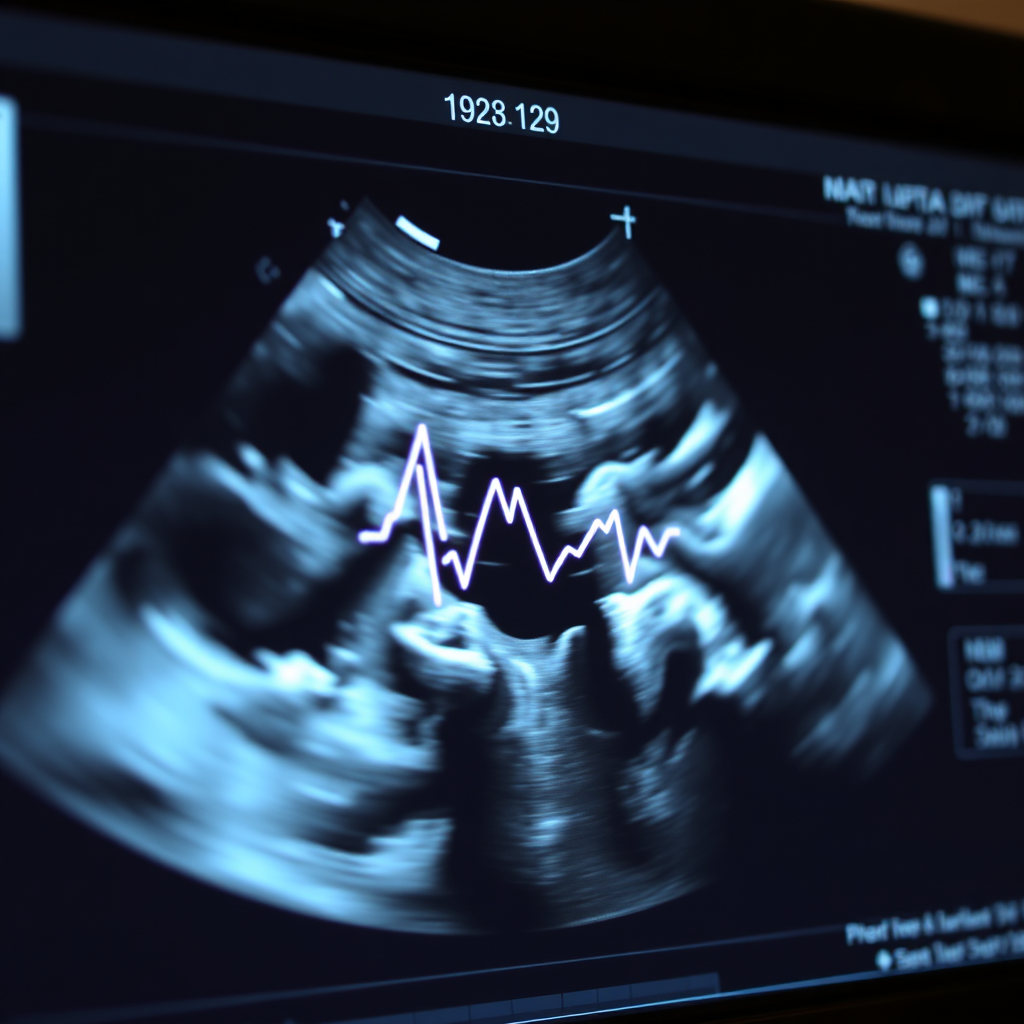

The real-time visual of the baby’s heartbeat and movement can be very impactful in reinforcing that there is life.

Ultrasound offers a unique glimpse into the womb, revealing the humanity and beauty of the developing child.